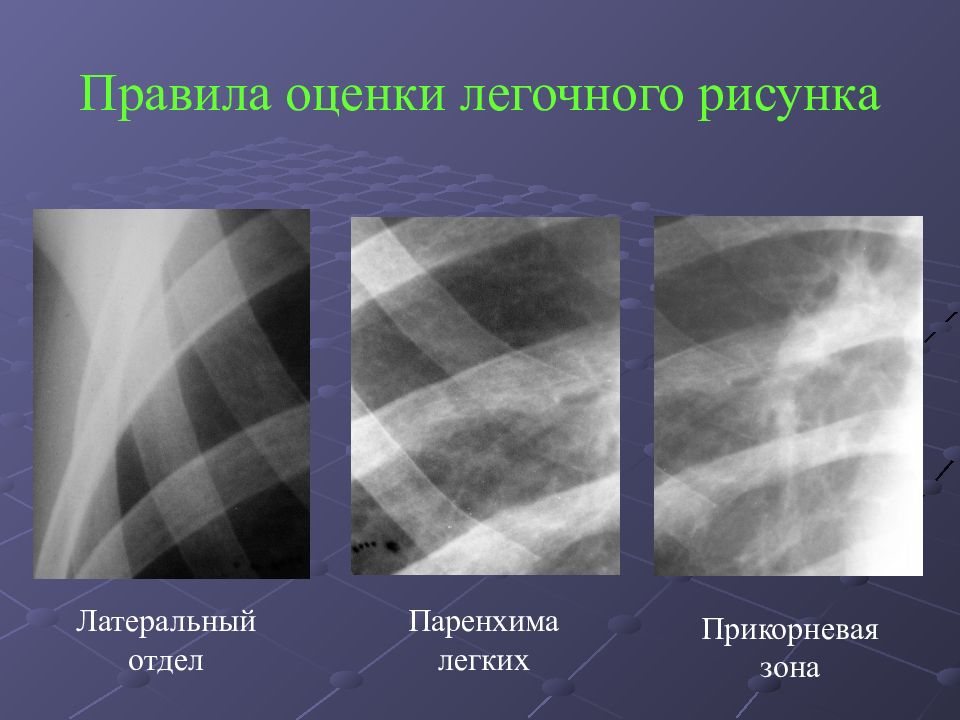

Фотографии, демонстрирующие обнаруженное усиление легочного рисунка

Раздел: Фотодневник открытий